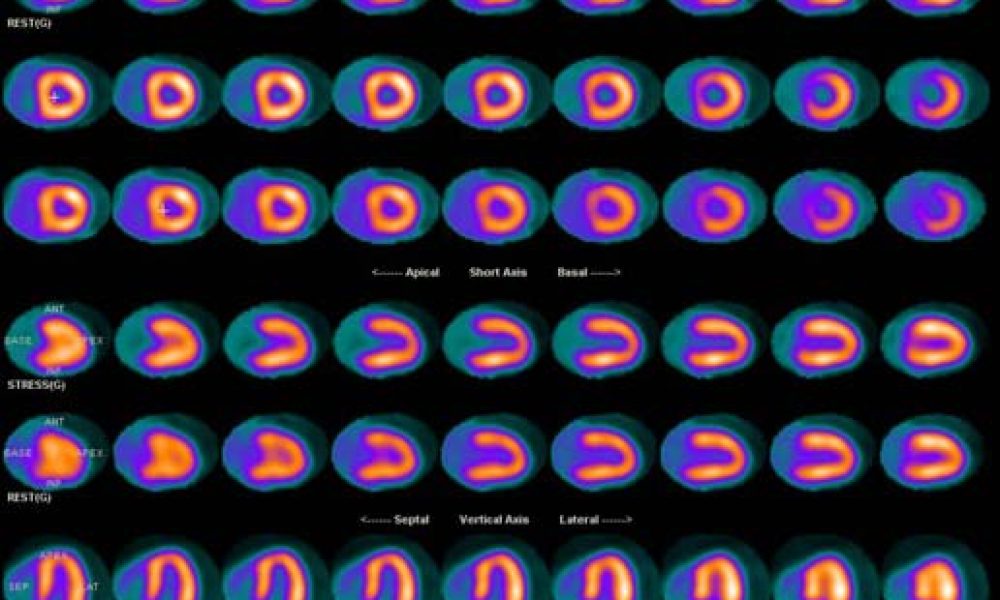

Are you looking for the nuclear medicine service and imaging equipment? Simplified Imaging Solution provides a complete turnkey solution to help your nuclear medicine facility to get through any challenge.